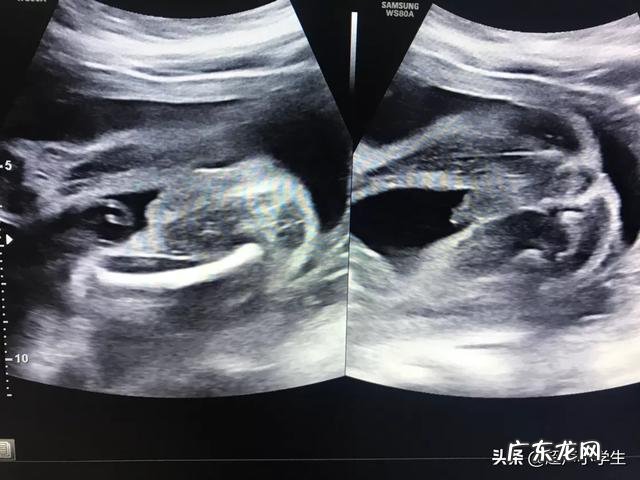

生男孩胎心率是每分钟多少下?记得我怀我家大宝和二宝的时候,每次产检最关心的就是胎心率,我家大宝男孩,二宝女孩,我来说说两者胎心率大概是多少 。

正常情况下胎心率为120~160次/分钟 。所以胎心率不会是一个固定的值,而是在一般在安全范围内浮动 。既然不是固定的值,就会有高有低,我们在检查报告上看到的胎心率的值只是胎儿某一时刻的胎心率值 。

一般来讲宝宝动的时候胎心率高一点,宝宝睡着了胎心率低一点,胎心率是真的和性别没有关系 。